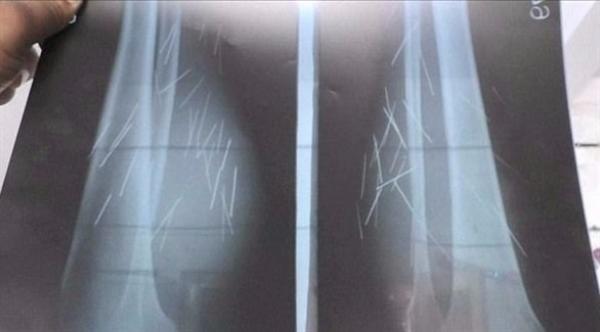

العثور على 70 إبرة داخل ساقي هذه المرأة